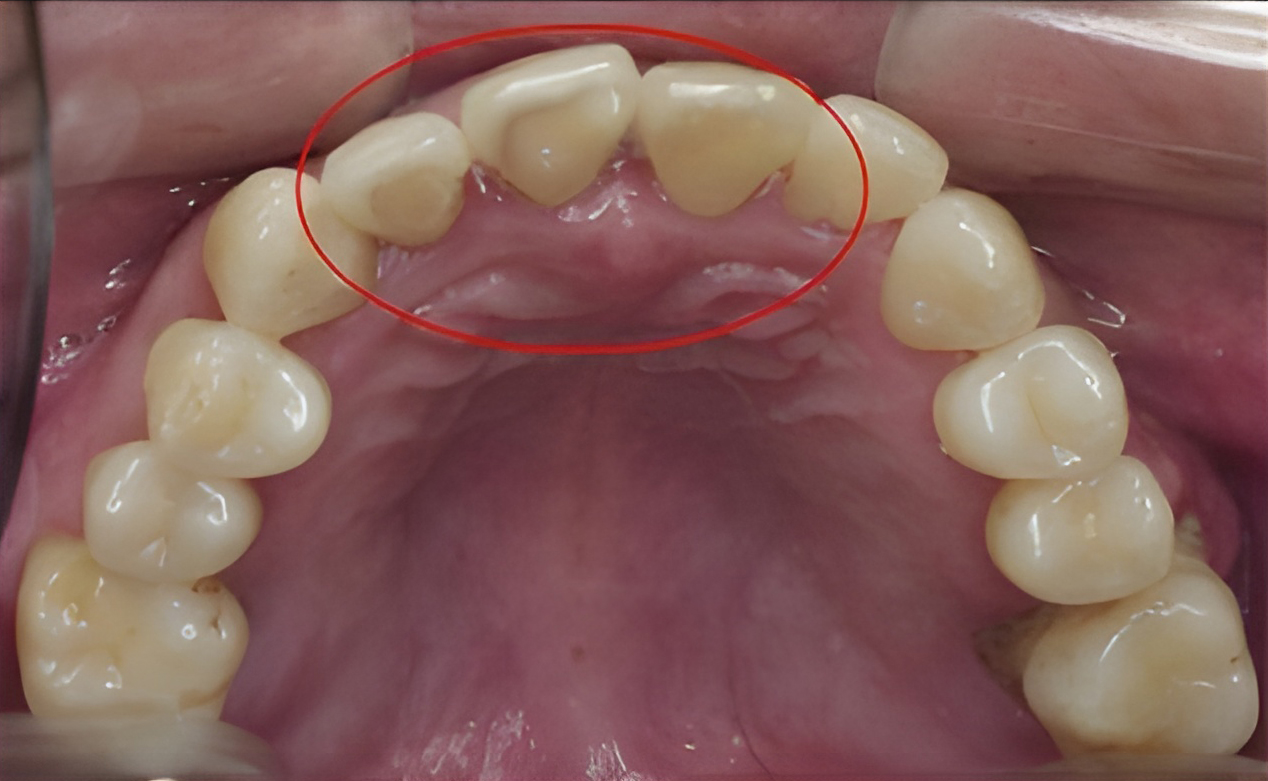

After

When it comes to dental treatment, nothing is more important than preventive care. A regular dental check-up and teeth cleaning prevents the development of serious dental problems that can require costly treatments. During a teeth cleaning, our licensed dental hygienist removes soft and hard deposits from your teeth and polishes the surfaces of your teeth.

It is recommended that you visit a dentist regularly once every six months. We send out a reminder for your next check-up appointment so you can maintain proper oral hygiene.